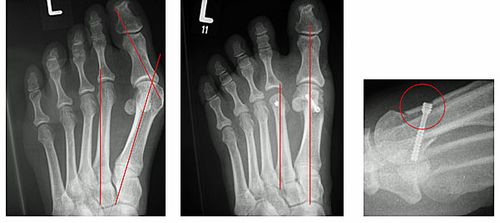

Abb.9: a Fixierte Krallenzehenfehlstellung mit Clavus (Hühnerauge). b Der störende Knochen wird entfernt (Resektionsarthroplastik nach Hohmann) Eine weitere Begleiterkrankung des Spreizfußes ist die Metatarsalgie. Es handelt sich um ein weit verbreitetes Beschwerdebild bei dem es zu belastungsabhängigen Schmerzen unter den Mittelfußköpfchen kommt. In fortgeschrittenen Stadien der Erkrankung ist eine Schwielenbildung sichtbar. Die Beschwerden können in den Anfangsstadien mit einer Einlage nach Maß und einer Schmetterlingsrolle am Schuh gut behandelt werden. Bestehen bei ausgeschöpfter konservativer Therapie noch Beschwerden erfolgt eine operative Verlagerung der Mittelfußköpfchen um den Druck unter dem Vorfuß zu reduzieren.

Abb.10: a Schmerzhafte Schwielenbildung unter dem Vorfuß.

b Wiederherstellung der Längenverhältnisse zwischen dem ersten, zweiten und dritten Strahl durch eine Rückverlagerung der Mittelfußköpfchen zwei und drei. Zeitgleich wurde auch der Hallux valgus korrigiert.